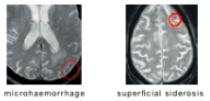

ARIA-H (mikroblödningar och sideros)

Plasmaläckage syns på FLAIR-sekvenser (Fluid-Attenuated Inversion Recovery) vid MR medan mikroblödningar och sideros detekteras på T2*-viktad MR, se tabell nedan för en diagnostisk jämförelse mellan ARIA-E och ARIA-H.1,2,4

T2*-GRE![]() |

| Diagnostiska fynd | Förhöjd signalintensitet på FLAIR-bilder, ingen diffusionbegränsning2 | Väldigt låg signalintensitet på T2*GRE-bilder1,4 |

| Karaktär på läckageprodukter | Proteinrika vätskor4 | Nedbrytningsprodukter av blod4 |

Parenkym: mikroblödningar (<10 mm), makroblödning (≥ 10 mm) Leptomeninger: ytliga hemosiderinavlagringar (ytlig sideros)4 |